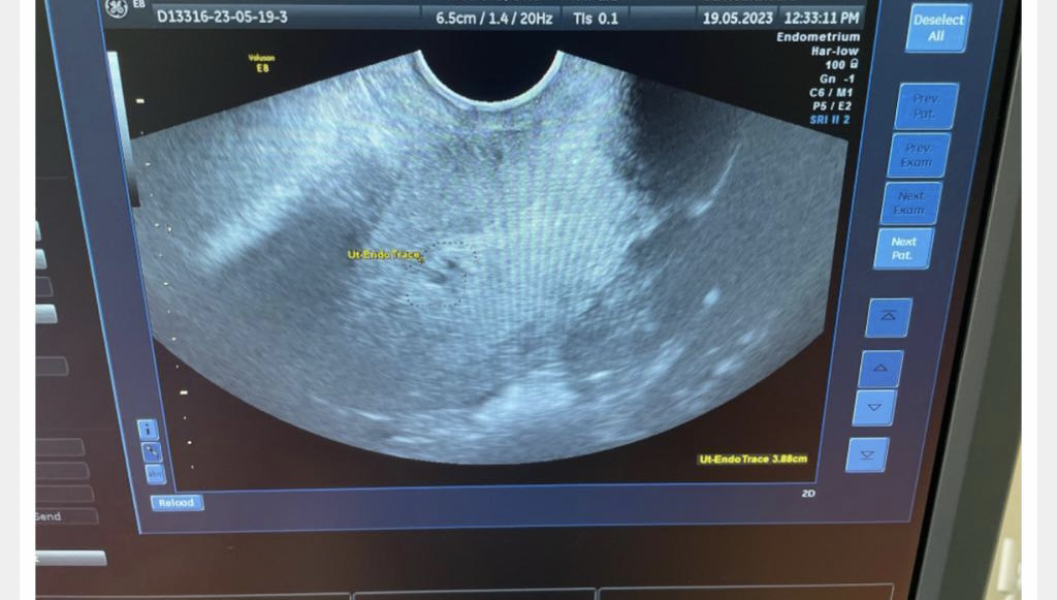

Not that it matters, I'm just wondering, do you think this but I've circled in pink is the fibroid? At 12 weeks it measured 3.5cm and if what I've circled is the fibroid it looks like it's not got bigger, which would be good. The doctor didn't mention it at all today as Prof A is looking properly next week.

@seven201 Thank you. How awful to have got all those bugs at once! Thanks for the tip, that's good to know - I've been checking my temp and it's ok. I'm glad your scan went well yesterday - such lovely photos! I don't know anything about fibroids, but what you've circled does look like it could be it - if so, glad it hasn't got any bigger and all is well x

@seven201 gorgeous pics! Sorry - I just looked and the fibroid and didn't notice the baby!! Congrats

@seven201 I'm not sure about the fibroid, but looks like it's quite far out, it's in the muscle I take it?